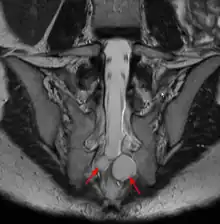

| MRI image showing a Tarlov cyst | |

Tarlov cysts, are type II innervated meningeal cysts, cerebrospinal-fluid-filled (CSF) sacs most frequently located in the spinal canal of the sacral region of the spinal cord (S1–S5) and much less often in the cervical, thoracic or lumbar spine. They can be distinguished from other meningeal cysts by their nerve-fiber-filled walls. Tarlov cysts are defined as cysts formed within the nerve-root sheath at the dorsal root ganglion.[2] The etiology of these cysts is not well understood; some current theories explaining this phenomenon have not yet been tested or challenged but include increased pressure in CSF, filling of congenital cysts with one-way valves, inflammation in response to trauma and disease. They are named for American neurosurgeon Isadore Tarlov, who described them in 1938.[3]

Tarlov cysts are relatively uncommon when compared to other neurological cysts. Initially, Isadore Tarlov believed them to be asymptomatic, however as his research progressed, Tarlov found them to be symptomatic in a number of patients. These cysts are often detected incidentally during MRI or CT scans for other medical conditions. They are also observed using magnetic resonance neurography with communicating subarachnoid cysts of the spinal meninges. Cysts with diameters of 1 cm or larger are more likely to be symptomatic; although cysts of any size may be symptomatic dependent on location and etiology. Some 40% of patients with symptomatic Tarlov cysts can associate a history of trauma or childbirth.[4] Current treatment options include CSF aspiration, fibrin-glue therapy, laminectomy with wrapping of the cyst, among other surgical treatment approaches. Interventional treatment of Tarlov cysts is the only means by which symptoms might permanently be resolved due to the fact that the cysts often refill after aspiration. Tarlov cysts often enlarge over time, especially if the sac has a check valve type opening. They are differentiated from other meningeal and arachnoid cysts because they are innervated and diagnosis can in cases be demonstrated with subarachnoid communication.

Tarlov cysts are most commonly located in the S1 to S4/S5 region of the spinal canal, but can be found along any region of the spine. They usually form on the extradural components of sacrococcygeal nerve roots at the junction of dorsal root ganglion and posterior nerve roots and arise between the endoneurium and perineurium.[10] Occasionally, these cysts are observed in the lumbar and thoracic spine.[7] However, these cysts most commonly arise at the S2 or S3 junction of the dorsal nerve root ganglion.[11][12] The cysts are often multiple, extending around the circumference of the nerve, and can enlarge over time to compress neighboring nerve roots, to cause bone erosion.[13] The cysts may be found anterior to the sacral area and have been known to extend into the abdominal cavity. These cysts, though rare, can be found to grow large - over 3–4 centimetres (1.2–1.6 in) in size, often causing severe abdominal pain from compression on the cyst itself as well as adjoining nerves.

MRI, or Magnetic Resonance Imaging, is considered the imaging study of choice in identifying Tarlov cysts. MRI provides better resolution of tissue density, absence of bone interference, multiplanar capabilities, and is noninvasive. Plain films may show bony erosion of the spinal canal or of the sacral foramina. On MRI pictures, the signal is the same as the CSF one.